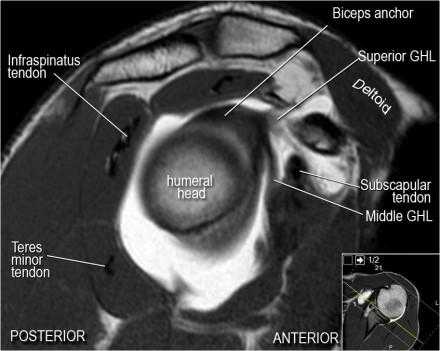

Нормальная анатомия плечевого сустава в аксиальных изображениях и контрольный список.

- поищите os acromiale, акромиальную кость (добавочная кость, расположенная у акромиона)

- обратите внимание что ход сухожилия надостной мышцы параллелен оси мышцы (это не всегда так)

- обратите внимание что ход сухожилия длинной головки двуглавой мышцы в области прикрепления направлен на 12 часов. Область прикрепления может быть различной ширины.

- обратите внимание на верхние отделы суставной губы и прикрепление верхней плече-лопаточной связки. На данном уровне ищется SLAP-повреждение (Superior Labrum Anterior to Posterior) и варианты строения в виде отверстия под сутавной губой (sublabral foramen - подгубное отверстие). На этом же уровне по задне-боковой поверхности головки плечевой кости визуализируются повреждение Хилл-Сакса.

- волокна сухожилия подлопаточной мышцы, создавая бицепитальную борозду, удерживают сухожилие длинной головки двуглавой мышцы. Изучите хрящи.

- уровень средней плече-лопаточной связки и передних отделов суставной губы. Поищите комплекс Буффорда. Изучите хрящи.

- вогнутость заднебокового края головки плечевой кости не следует путать с повреждением Хилл-Сакса, поскольку это нормальная форма для данного уровня. Повреждение Хилл-Сакса визуализируется только на уровне клювовидного отростка. В предних отделах мы сейчас на урвоне 3-6 часов. Здесь визуализируются повреждение Банкарта и его варианты.

- обратите внимание на волокна нижней плече-лопаточной связки. На данном уровне так же ищется повреждение Банкарта.

Нормальная сагиттальная анатомия и контрольный список

- обратите внимание на мышцы манжеты вращателей и поищите их атрофию

- обратите внимание на среднюю плече-лопаточную связку, которая имеет косое направление в полости сустава, и изучите отношение к сухожилию подлопаточной мышцы

- на данном уровне иногда видны повреждения суставной губы в направлении на 3-6 часов

- изучите место прикрепления длинной головки двуглавой мышцы плеча к суставной губе (biceps anchor)

- обратите внимание на форму акромиона

- поищите импинджмент за счет акромиально ключичного сустава. Обратите внимание на интервал между мажетой вращателей и клювовидно-плечевой связкой (coracohumeral ligament).

- поищите повреждение подостной мышцы